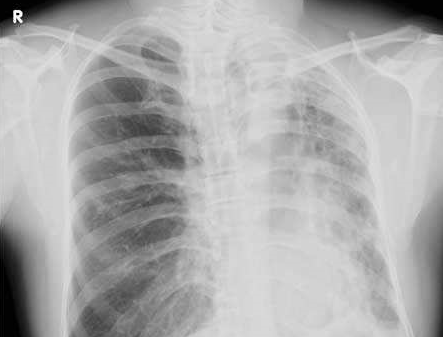

肺脹的發(fā)病原因有哪些?肺脹的癥狀表現(xiàn)及其預(yù)防

肺脹,屬肺病。常繼發(fā)于肺咳、哮病等之后,因肺氣長期壅滯,肺葉恒久膨脹、不能斂降,而脹廓充胸。以胸中脹悶、咳嗽咳痰、氣短而喘為主要表現(xiàn)的肺系疾病。

1.發(fā)病原因肺脹的圖片

肺脹的發(fā)病原因

肺脹的癥狀